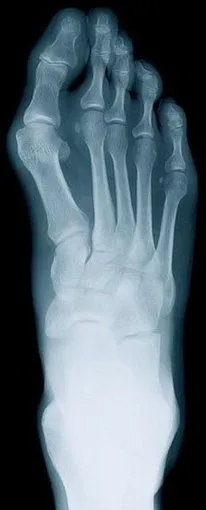

Rheumatoid Arthritis

Rheumatoid arthritis, otherwise known as RA, is a chronic disease. The disease causes inflammation of the lining of the joints. This disease can lead to long-term joint damage which in turns results in chronic pain, loss of function and disability.

RA advances through three stages:

The first stage causes swelling of the synovial lining, producing pain, a warming sensation, stiffness, redness and swelling around the joint.

The second stage causes rapid division and growth of cells which causes the synovium lining to thicken.

In the third stage, the inflamed cells release enzymes that may digest bone and cartilage, often causing the infected joint to lose its shape and alignment. This also causes more pain and some loss of movement.

There is no cure for RA and frequent flares in disease activity occur spontaneously. RA can also begin to affect other organs in the body. However, studies have shown that early aggressive treatment of RA can limit joint damage, somewhat eliminating loss of movement, decreased ability to work, and potential surgery.